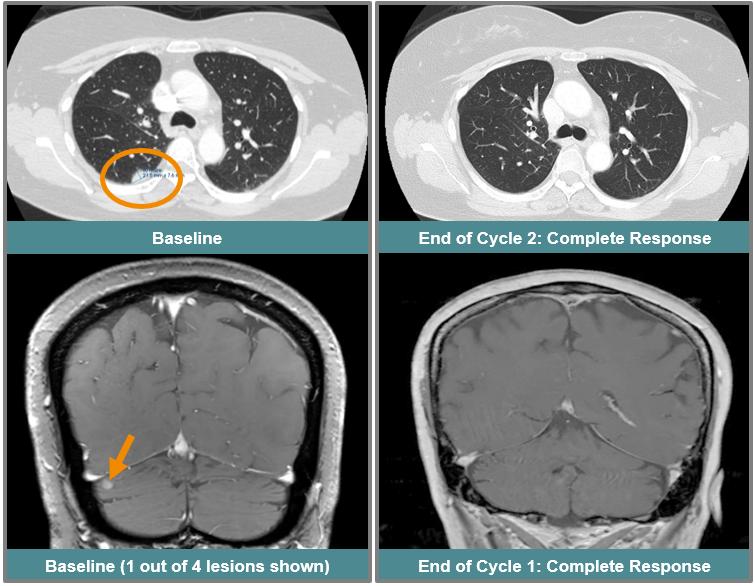

This patient, a 55-year-old woman with EGFR exon 20 mutated NSCLC previously treated and progressed on platinum-based chemotherapy followed by amivantamab, had four active CNS non-target lesions at study entry that had not been previously treated with either surgery or radiation. The patient received 75 mg once daily of ORIC-114, and by the end of the first cycle had a 60% reduction in all systemic target lesions, which improved to a complete response at the next cycle, with 100% reduction of all target lesions and disappearance of non-target lesions. The complete response was subsequently confirmed. The patient also had a complete response of all CNS disease after the first cycle with complete resolution of all four CNS lesions, which was also confirmed at a later scan.

Confirmed intracranial and systemic response in a patient with EGFR exon 20 mutated NSCLC and active CNS metastases that progressed on prior EGFR exon 20 targeted therapy.

img260370254_16.jpg